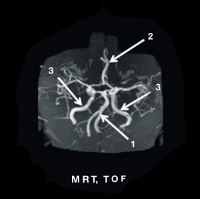

MRT TOF

mrt_02

1. erweiterete A. basilaris

2. A. cerebri anterior

3. A. carotis interna geschlängelte und dilatierte Blutgefäße

Mit freundlicher Genehmigung von Prof. Dr. Arndt Rolfs, Universität Rostock